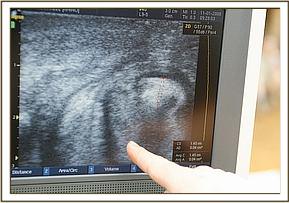

Dr.Goodhead believes that this is most likely a degenerating developmental defect from birth - as the ultra sound revealed that not only did he have cataracts, but he had a hyperechoic mass in the anterior part of the globe and then the posterior segment of the globe was filled with extremely dense point-like hyperechoic masses. These masses suggest cellular material filling the entire posterior segment and on movement of the globe this mass which could be blood and degenerate cells could be seen moving about. The retina also appeared to be detached as well. Hence no amount of surgery could ever restore sight to Maxwell. We had Shida in the next door stockade and were able to examine his eyes with the ultrasound as a comparison to those of Maxwell, and the marked difference was clearly visible.